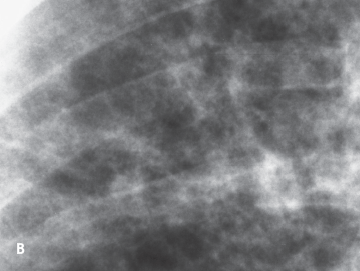

Fifteen months after his initial presentation, however, an MRI scan showed progression of tumor. The patient had no neurologic complaints, and seizures were well controlled. A review of systems revealed a persistent nonproductive cough of 2 months’ duration, and a chest roentgenogram, seen here (A and B), was obtained. The patient reported an ongoing history of smoking two packs of cigarettes a day.

The chest film (A and B) demonstrates diffuse bilateral nodular opacities, some of which are cavitary. The bases are relatively spared. No pleural effusion or hilar or mediastinal adenopathy is evident. The primary diagnostic consideration is disseminated infection; other possibilities include sarcoidosis, Wegener’s granulomatosis, and metastatic disease.

A chest CT scan (C) demonstrated a diffuse distribution of small nodules with ill-defined margins. Some of the lesions contain central cavitation (D, arrow). Transbronchial lung biopsy was inconclusive. Thoracoscopic lung biopsy samples showed abundant Langerhans’ cells within areas of dense fibrosis, confirming the diagnosis.